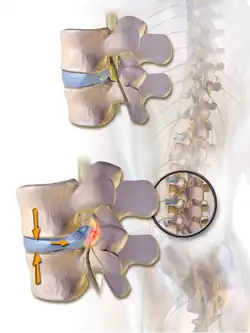

Normal situation and spinal disc herniation in cervical vertebrae

Normal situation and spinal disc herniation in cervical vertebrae -

Illustration depicting herniated disc and spinal nerve compression

Illustration depicting herniated disc and spinal nerve compression -